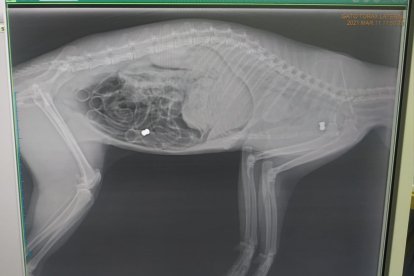

Más gatos explorados para comprobar los disparos.